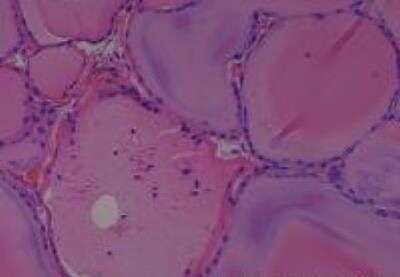

Scientific Data Images for Human Multi Tissue MicroArray (Normal Adjacent)

Hematoxylin & Eosin Stain: Human Common Tissue MicroArray (Normal Adjacent) [NBP2-30215] - 103. Stomach